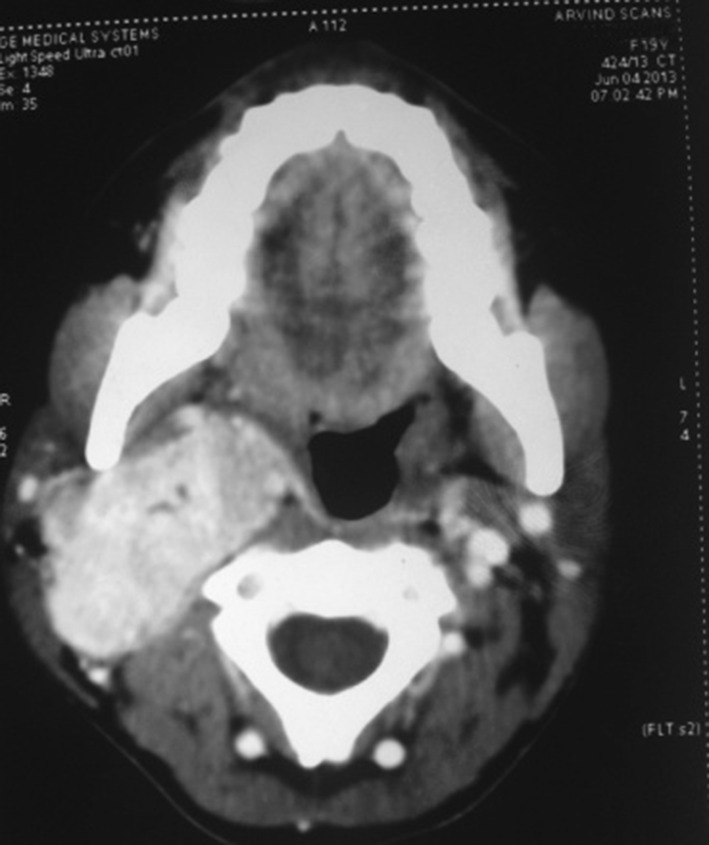

CT scan revealed a well defined, ovoid intensely enchasing isodense, solid mass over the posterior styloid compartment of right para pharyngeal space with splaying of carotid bifurcation and encasement of right internal carotid artery. The size of the lesion was around 5 cm supero-inferiorly and 4 cm in diameter i.e. medio-laterally.

Fig. 2.

CT scan showing the lesion splaying the ICA and ECA

Fig. 3.

Axial cut showing obliteration of pharyngeal space